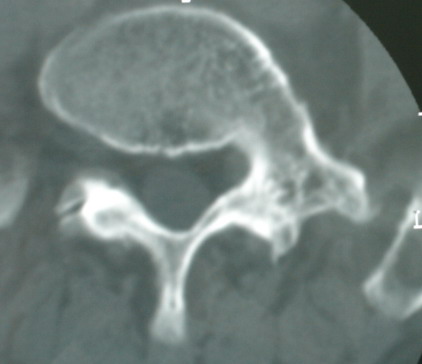

以下是引用jinguoji在2008-6-3 20:20:00的发言:[br]双上肺弥漫性小结节影,纵隔窗内钙化淋巴结影,考虑血播性tb可能性较大,不除外肺ca可能。腰椎考虑退变。

以下是引用卜一在2008-6-3 19:33:00的发言:[br]双肺结节,以双上肺分布为多,期间搀杂片状致密影及索条致密影。考虑:继发性肺结核伴血型播散可能性大。不除外肺泡ca的可能!另:椎体退变!

以下是引用panyishengct在2008-6-3 21:09:00的发言:[br]双上肺弥漫性小结节影,纵隔窗内钙化淋巴结影,考虑矽肺或/和tb可能性较大,不除外肺ca可能。腰椎考虑退变。 [br][br]